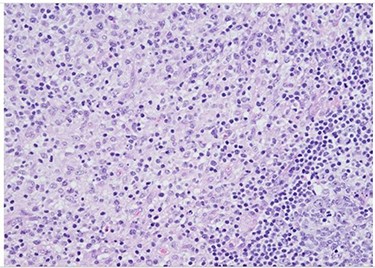

H&E slide (medium magnification, 20×) shows activated lymphocytes, immunoblasts and plasmacytoid monocytes.

H&E (High power magnification, 40×) shows characteristic large activated lymphoid cells, karyorrhectic debris and histiocytes. The histiocytes are enlarged with crescentic nuclei and phagocytized nuclear debris. Neutrophils are absent.